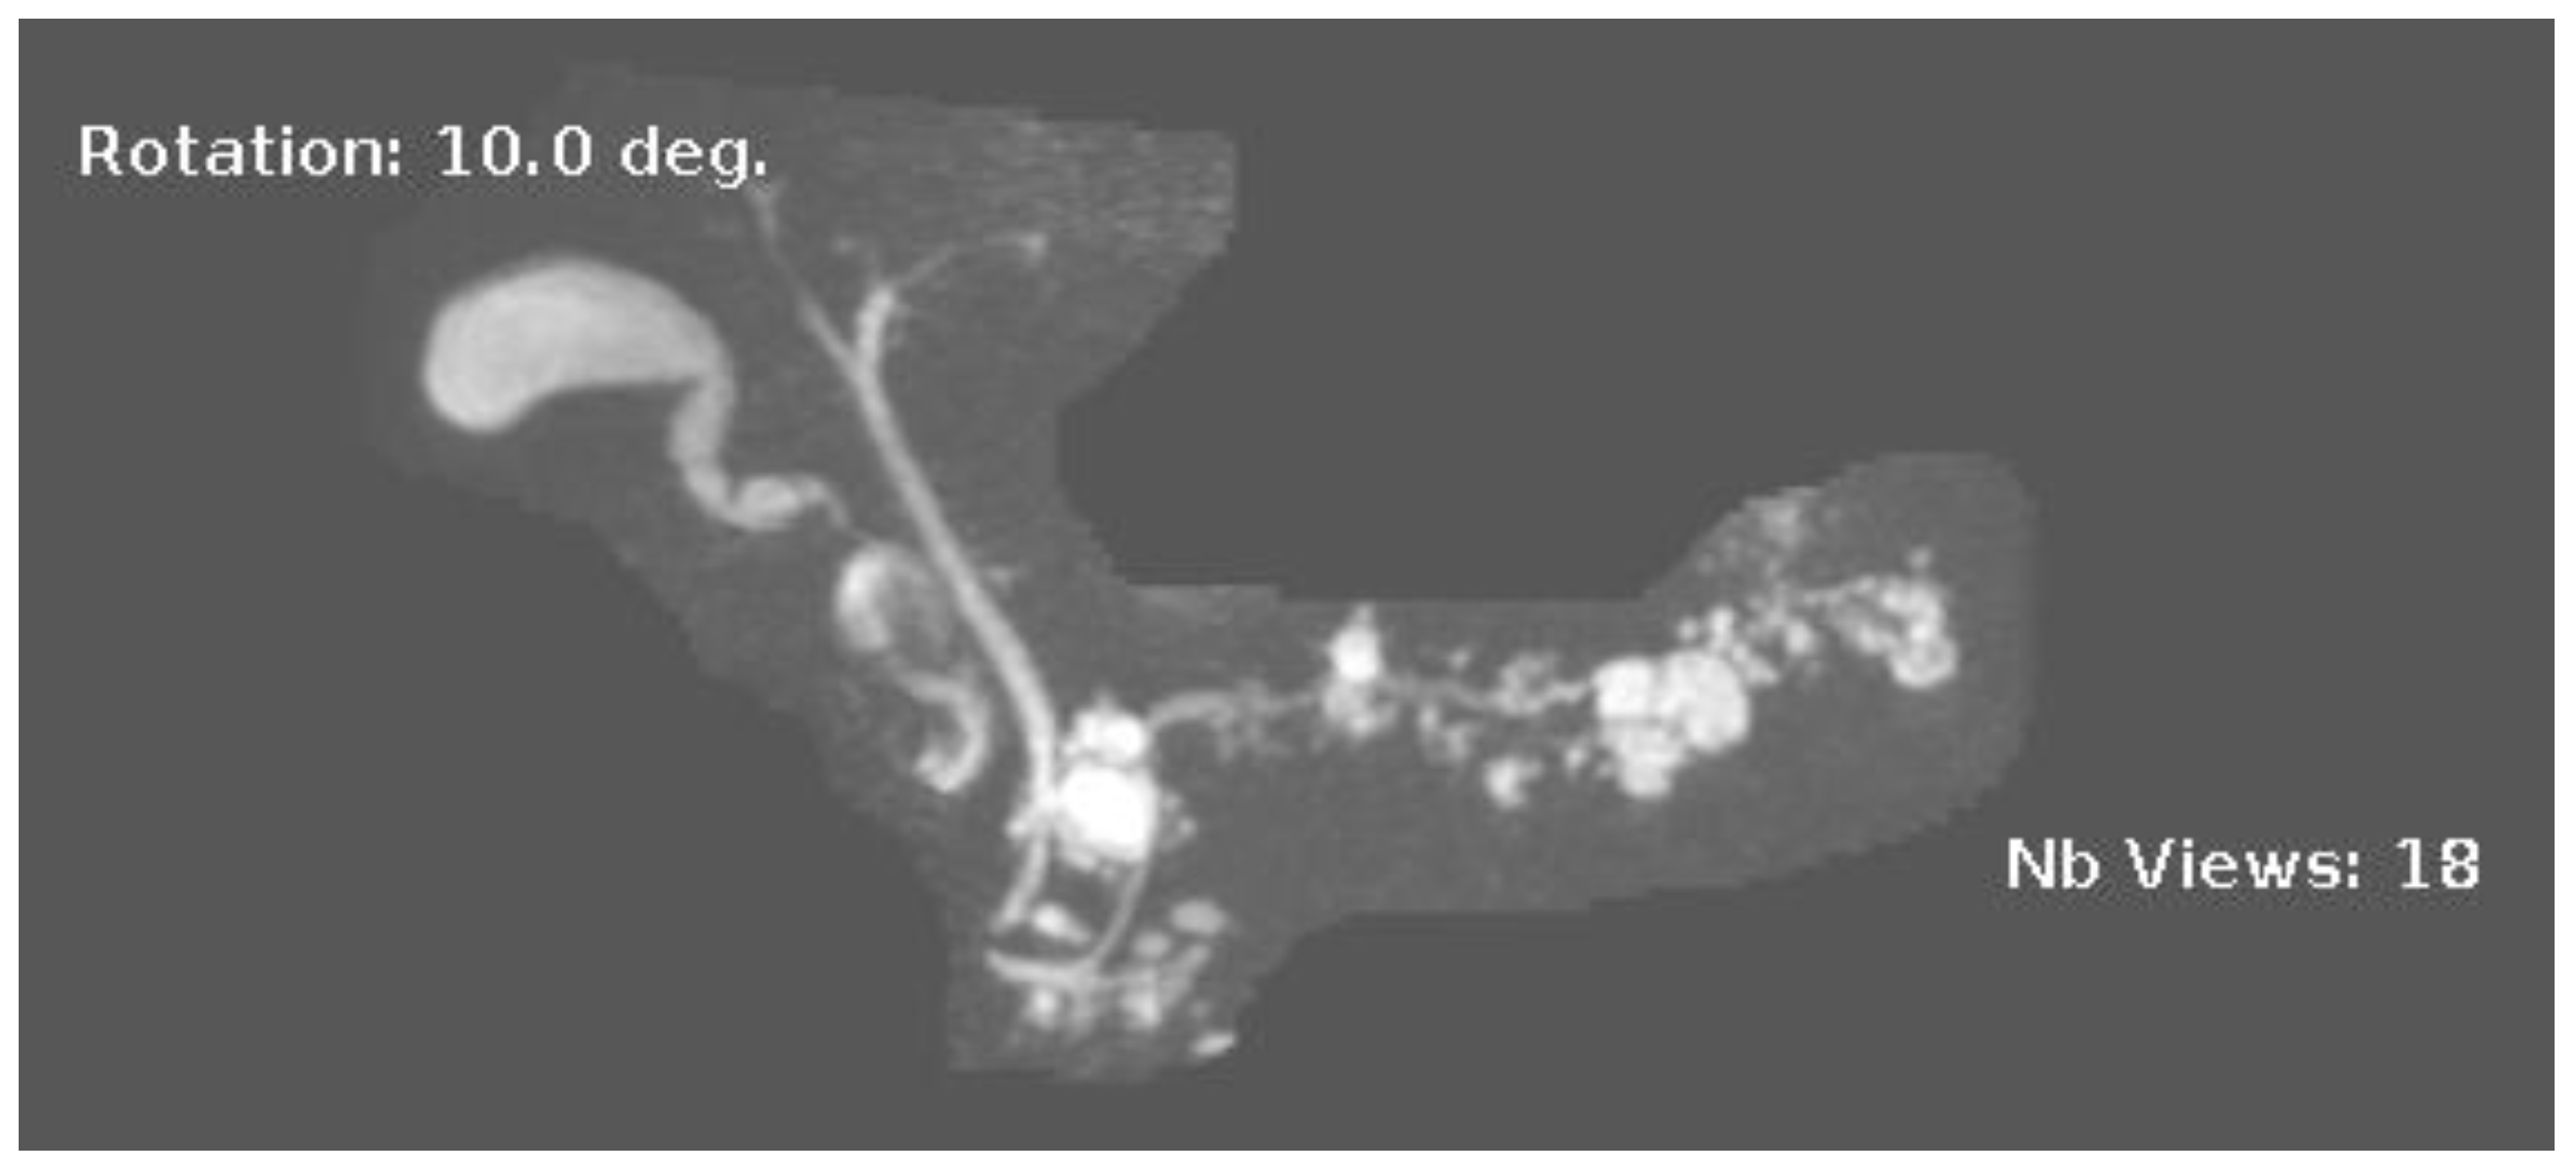

IPMNs can be divided into main duct intraductal papillary mucinous neoplasm and branch duct intraductal papillary mucinous neoplasms, with dilation of the main pancreatic duct helping to distinguish between the two. They usually present in the fifth to seventh decade of life and have an equal distribution between males and females [15]. Intraductal neoplasms are typically associated with a dilated main pancreatic duct (Figure 2a,b), whereas the branch duct IPMNs are associated with a dilated pancreatic duct branch or branches (Figure 3). A mixed IPMN is defined as a cystic lesion with ductal communication and main pancreatic duct dilation greater than or equal to 5 mm (Figure 4). Diabetes mellitus (DM) and a family history of pancreatic adenocarcinoma are known risk factors for IPMN, with odds ratios of 1.79 (CI 95%: 1.08–2.98) and 2.94 (CI 95%: 1.17–7.39), respectively [16]. Cytology can show columnar cells with variable atypia and can stain positive for mucin. CEA is usually greater than 200 ng/mL in approximately 75% of lesions, similar to mucinous neoplasms. Main duct IPMNs have a 36–100% risk of malignant potential, compared to a lower risk of 11–30% malignant potential of side branch IPMNs [17].

Figure 3.

MRI image of side branch IPMN.

Figure 4.

MRI image of mixed IPMN.